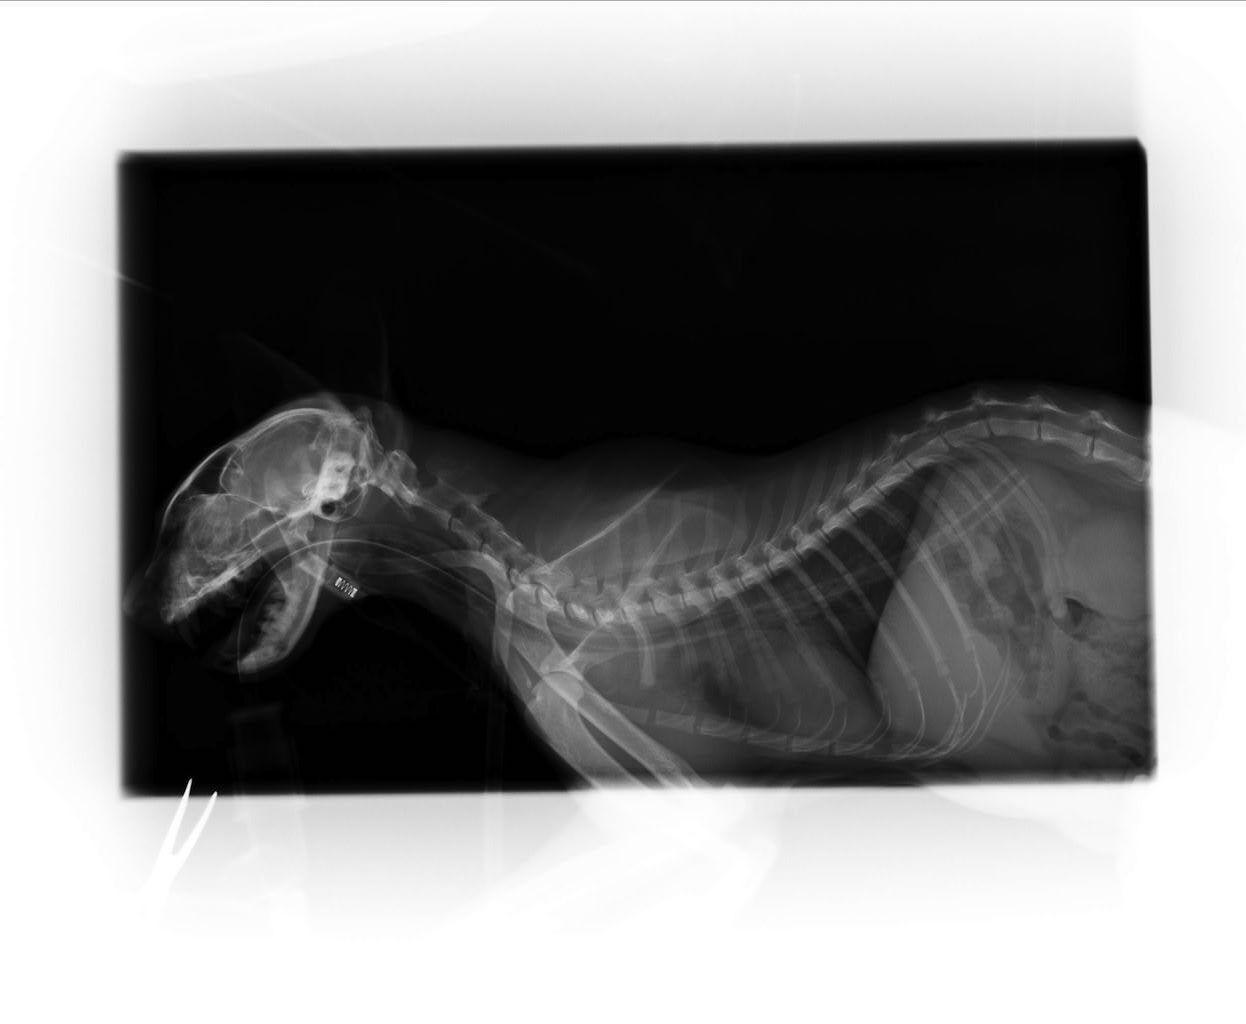

送到醫院做了血檢,發現阿花是慢性腎臟衰竭還嚴重脫水,當天驗出血中尿素跟肌酸酐都超標,後來給了幾天點滴後血紅素卻下降到10%以下而開始不吃不喝。當下就決定讓阿花輸血,同時放了食道胃管替阿花灌食,希望在透過治療後,也能像一般腎貓出院,繼續維持貓咪的生活品質。

在我能力範圍,我想要給浪貓的不只食物,更有機會是是醫療及後續的生活品質。期待大家的幫忙。動物近況說明: 8/23

從送阿花到恩澤到目前十多天,每天大致上阿花就是給點滴跟灌食,中間經歷了一次輸血,因為血紅素過低,輸完一次之後就只能靠點滴維生,嘗試移開點滴後腎臟的功能仍然很差無法恢復,在8/23這天去當小天使了,謝謝大家關心跟醫師的盡力,醫藥費部分請大家幫忙,感謝!!